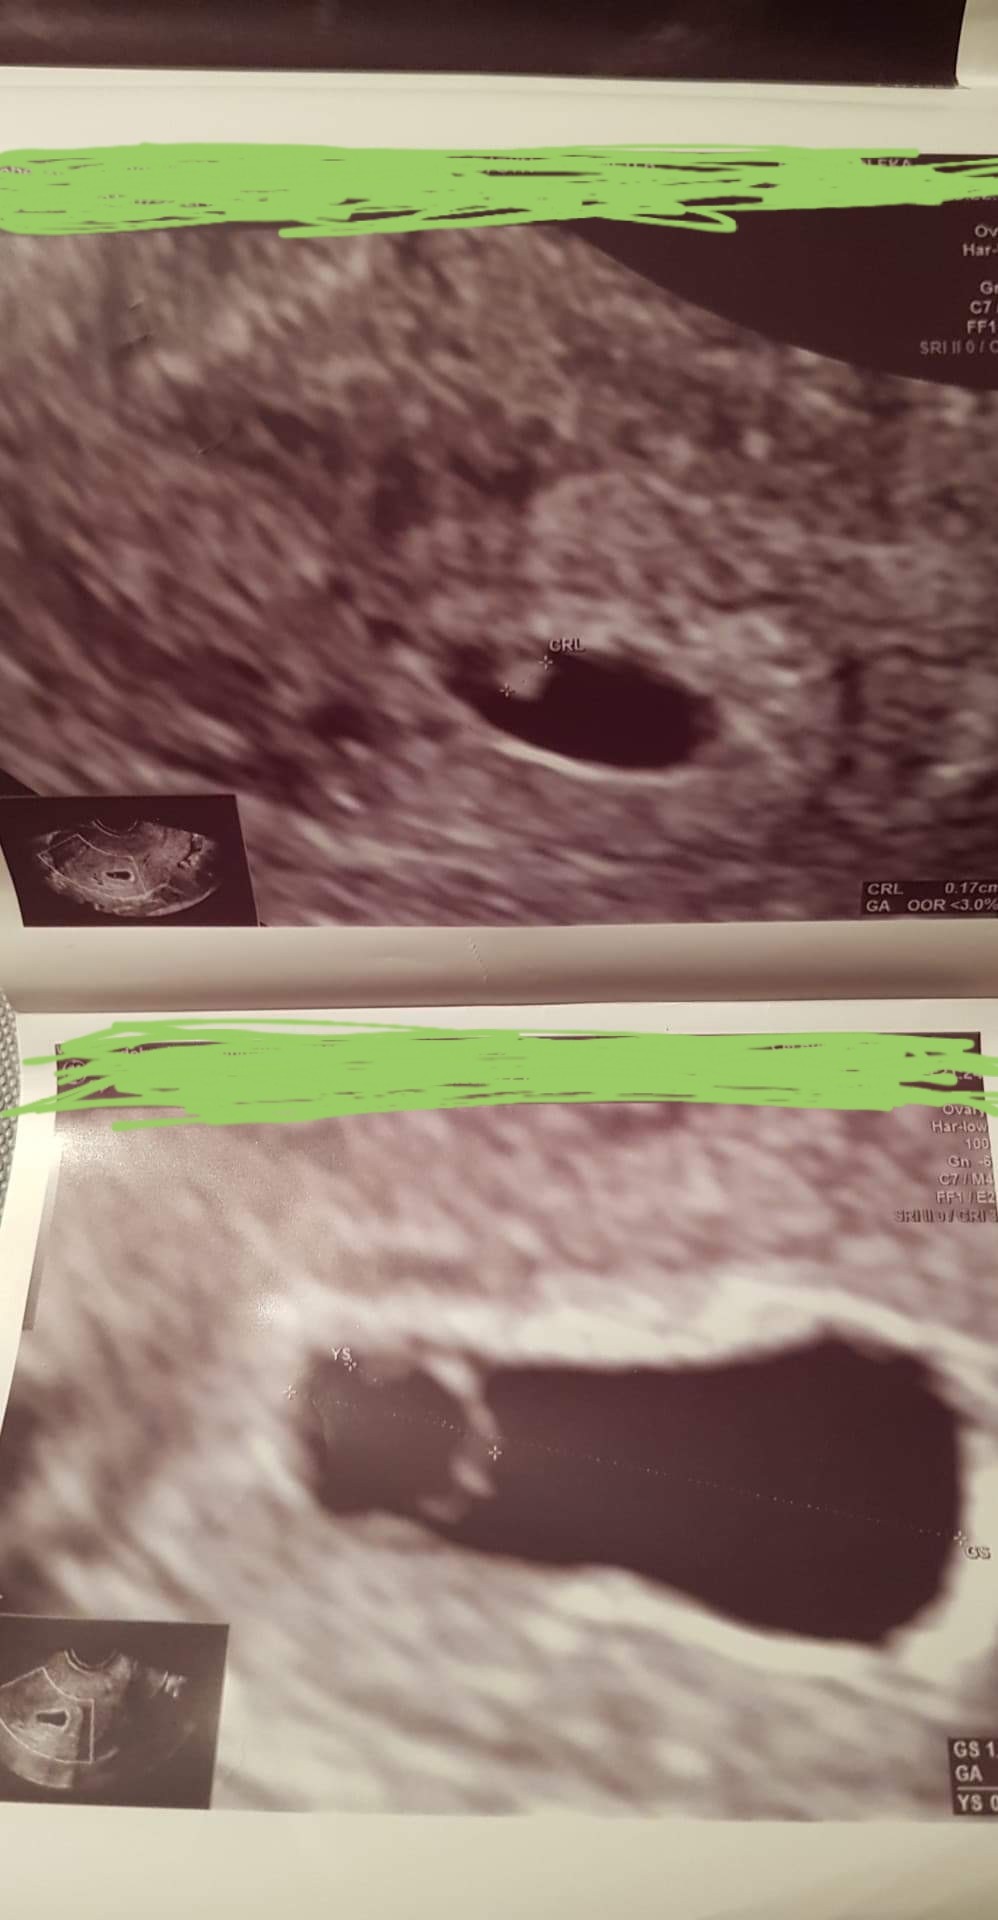

Super wiadomośćByłam na badaniach.

Serduszko bije.

Fasolka ma 1.7mm![]()